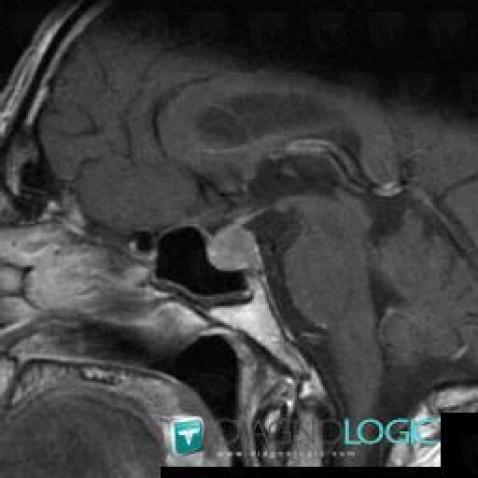

Pituitary macroadenoma, Pituitary gland and parasellar region, MRI

Here is the specific information in the key image above:

- Diagnosis Pituitary macroadenoma, Location(s) Pituitary gland and parasellar region, with gamuts Sellar and parasellar mass